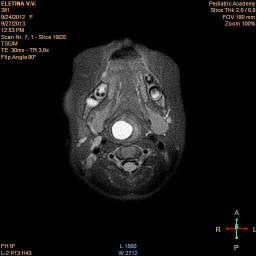

When fibro laryngoscopy revealed a rounded formation of the right vysokopalonadgortnaya fold almost completely overlapping the lumen of the larynx (Figure 1). On a series of MRI tomograms of the soft tissues of the neck from the level of C2 to the level of C5-6 in the projection of the right pear-shaped sinus is determined by a cyst with clear uneven contours, which has an irregular rounded shape. The size of the cyst is 11x16x28mm. Cyst significantly shifts the right scooped-nadgortnaya fold to the left. Its lower edge is traced at the level of the subglottic space (Figure 2-4).

Figure 3:MRI, coronary projection.